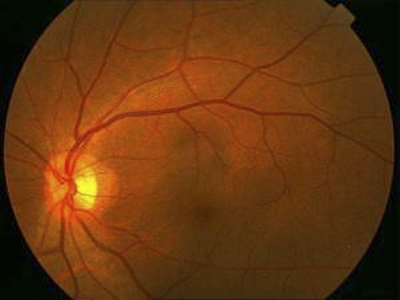

A:眼前出現飛蚊的症狀往往是因為玻璃體發生了液化、變性和混濁,通常情況下玻璃體的混濁,比較多見於近視眼的人和年歲比較大的中老年人,還要特別重視的一個問題是當眼底有病變發生的時候,也會出現玻璃體的混濁、玻璃體混濁的加重,這時候眼前飛蚊的症狀需要做……

A:眼睛裡有飛蚊的現象主要是因為玻璃體發生了液化、變性和混濁,玻璃體原本在眼睛裡邊是一個膠凍狀的結構,由於近視眼以及中高度近視或者年齡過大了,中老年人就會出現玻璃體的液化、變性和混濁,這種情況下很難通過任何治療,將已經液化的玻璃體恢復到膠凍狀的……